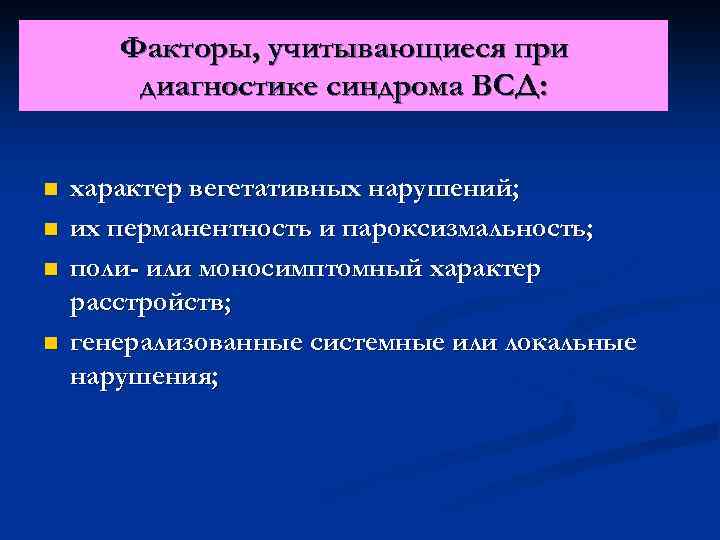

Факторы, учитывающиеся при диагностике синдрома ВСД: n n характер вегетативных нарушений; их перманентность и пароксизмальность; поли- или моносимптомный характер расстройств; генерализованные системные или локальные нарушения;